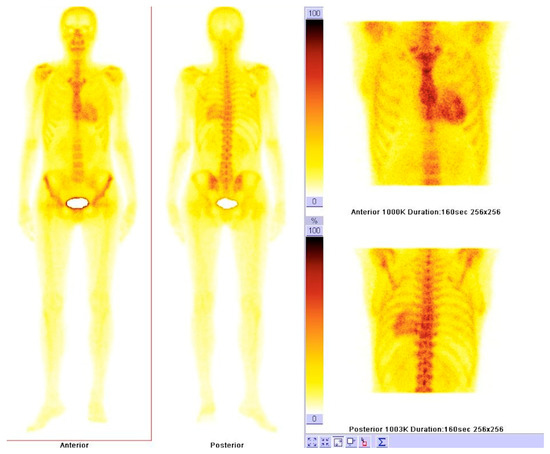

6. Nuclear Imaging

6.1. Nuclear Imaging in Amyloidosis

6.2. Nuclear Imaging in Sarcoidosis

6.3. Nuclear Imaging in Hemochromatosis